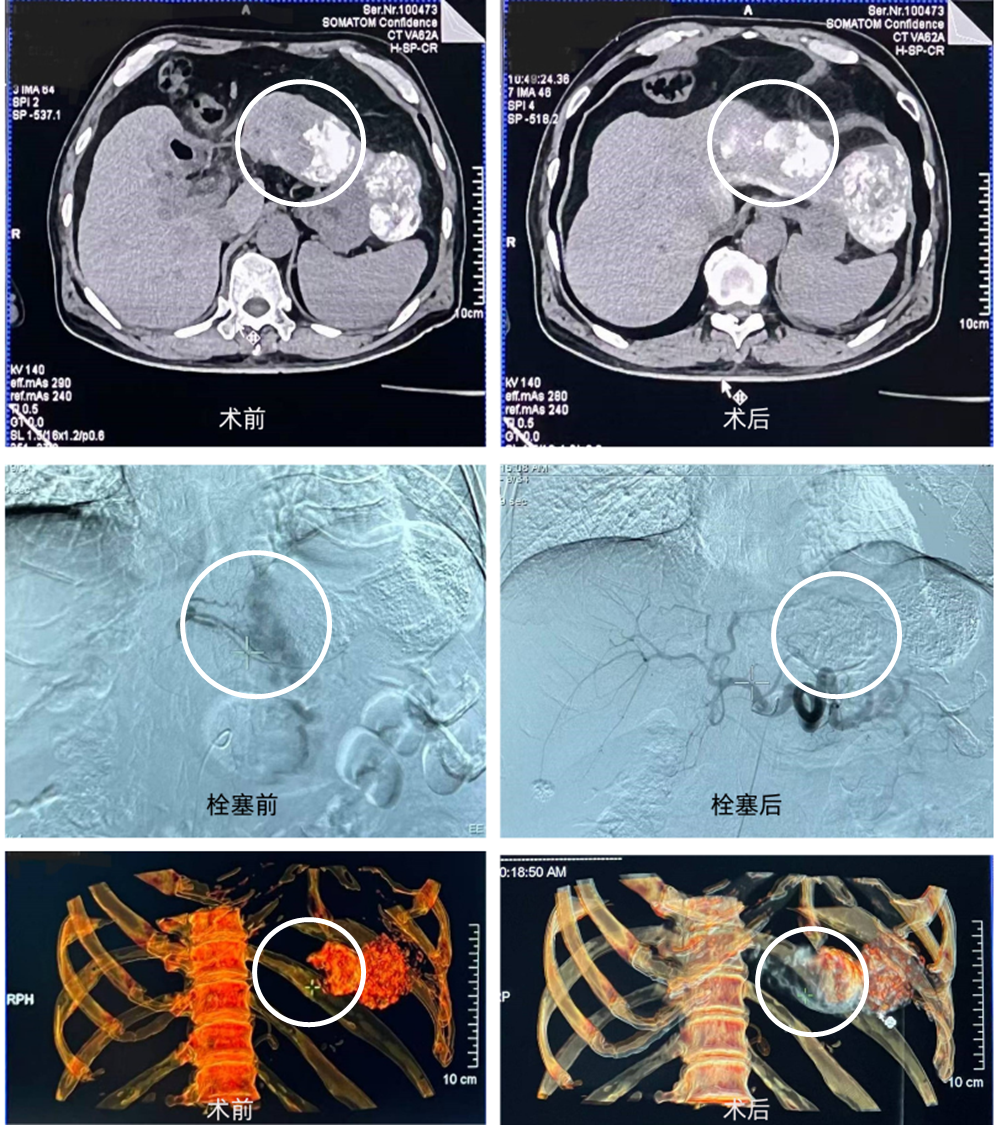

男性,62岁。肝脏原发性肿瘤,BCLC-B期(CNLC-Ⅱa期),此次治疗肿瘤直径5cm,肿瘤位于肝左叶第Ⅱ、Ⅲ段。拟行DEB-TACE治疗。

常规消毒铺巾,穿刺、置鞘,送入造影导管及2.2F微导管,造影确认肿瘤供血动脉。以闪渊聚乙烯醇栓塞微球(110µm)加载表柔比星,约3min完成药物加载。按体积比1:10将造影剂加入微球/药物混合液中,载药微球悬浮良好。在DSA影像下,将载药微球悬浮液以脉冲方式(1mL/min)注入目标血管。术后影像显示,栓塞良好。

影像资料

闪渊®TraSphere®均一粒径可视化栓塞微球载药迅速,悬浮性良好,术中推注顺畅,优于同类产品。与非均一粒径微球相比,对末梢血管的栓塞效果更优,且在达到栓塞终点时,用量更少。微球在DSA及CBCT下显影清晰,可用于术中判断是否出现异位栓塞并及时调整,对避免过量栓塞、假性栓塞,并完成栓塞边际具有较大的意义。期待更多临床应用,进一步探讨其优势与更多应用场景。